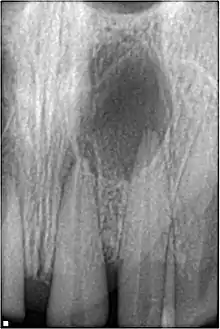

Pulpal obliteration

4-24% of traumatized teeth will have some degrees of pulpal obliteration that is characterized by the loss of pulpal space radiographically and yellow discolouration of the clinical crown. No treatment is needed if it is asymptomatic. Treatment options will be extraction for symptomatic primary tooth. For symptomatic permanent tooth, root canal treatment is often challenging due to pulp chamber is filled with calcified material and the ‘drop off’ sensation of entering a pulp chamber will not occur.[42]